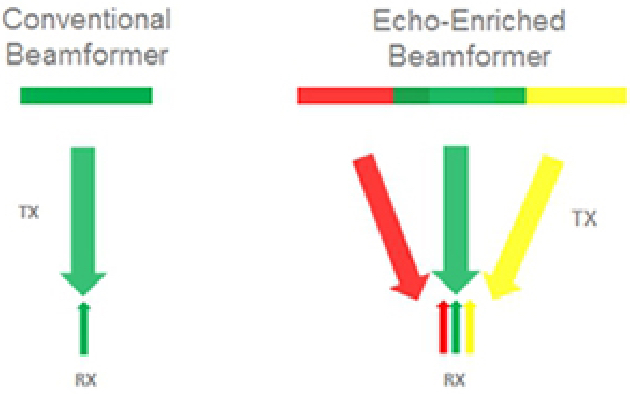

iBeam?

Permits use of multiple scanned angles to form a single image, resulting in enhanced contrast resolution and improved visualization.